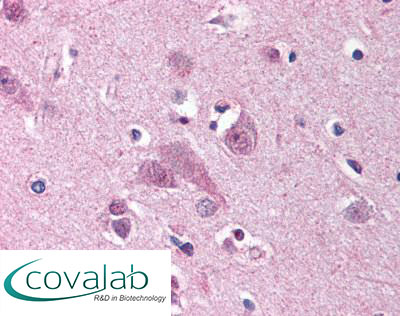

Anti-MARK1 antibody IHC staining of formalin-fixed, paraffin-embedded human cortex after heat-induced antigen retrieval.